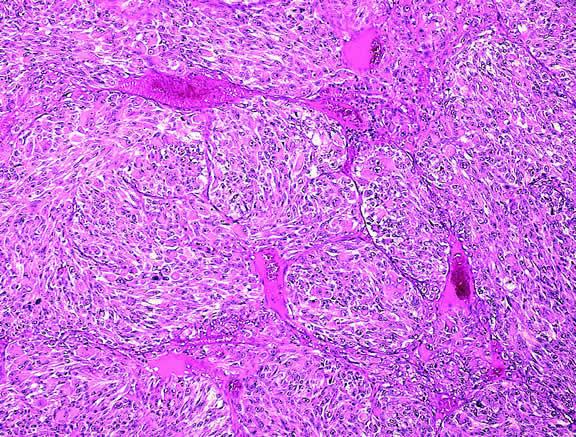

Histopathology

The cells comprising uveal melanoma constitute a biologic spectrum comprising bland spindle A melanoma cells at one end and wildly anaplastic epithelioid cells at the other. The term spindle cell is derived from the fusiform or spindled configuration of the cells' cytoplasmic outline. They are bipolar in shape, and many have long tapering processes that occasionally are highlighted when individual pigmented cells are seen in a largely amelanotic tumor. Spindle cells grow in a syncytial fashion forming interweaving fascicles of parallel oriented cells (Fig. 30). The cells can be pigmented or nonpigmented. Two types of spindle cells are recognized; spindle A and spindle B. These are distinguished by their nuclear characteristics. Spindle A nuclei are tapering ovals or cigar-shaped and have finely dispersed chromatin (Fig. 31). If a nucleolus is present, it usually is inconspicuous. Many spindle A cells have a longitudinally oriented chromatin stripe that actually is caused by a fold in the nuclear membrane. The nuclei of spindle B cells have distinct nucleoli and coarser chromatin and tend to be plumper and more oval in shape (Fig. 32).

Fig. 30. Amelanotic spindle cell melanoma. Tumor is composed of interweaving fascicles of spindle cells. Photomicrograph shows longitudinally and transversely sectioned fascicles. (Hematoxylin-eosin, × 100.)